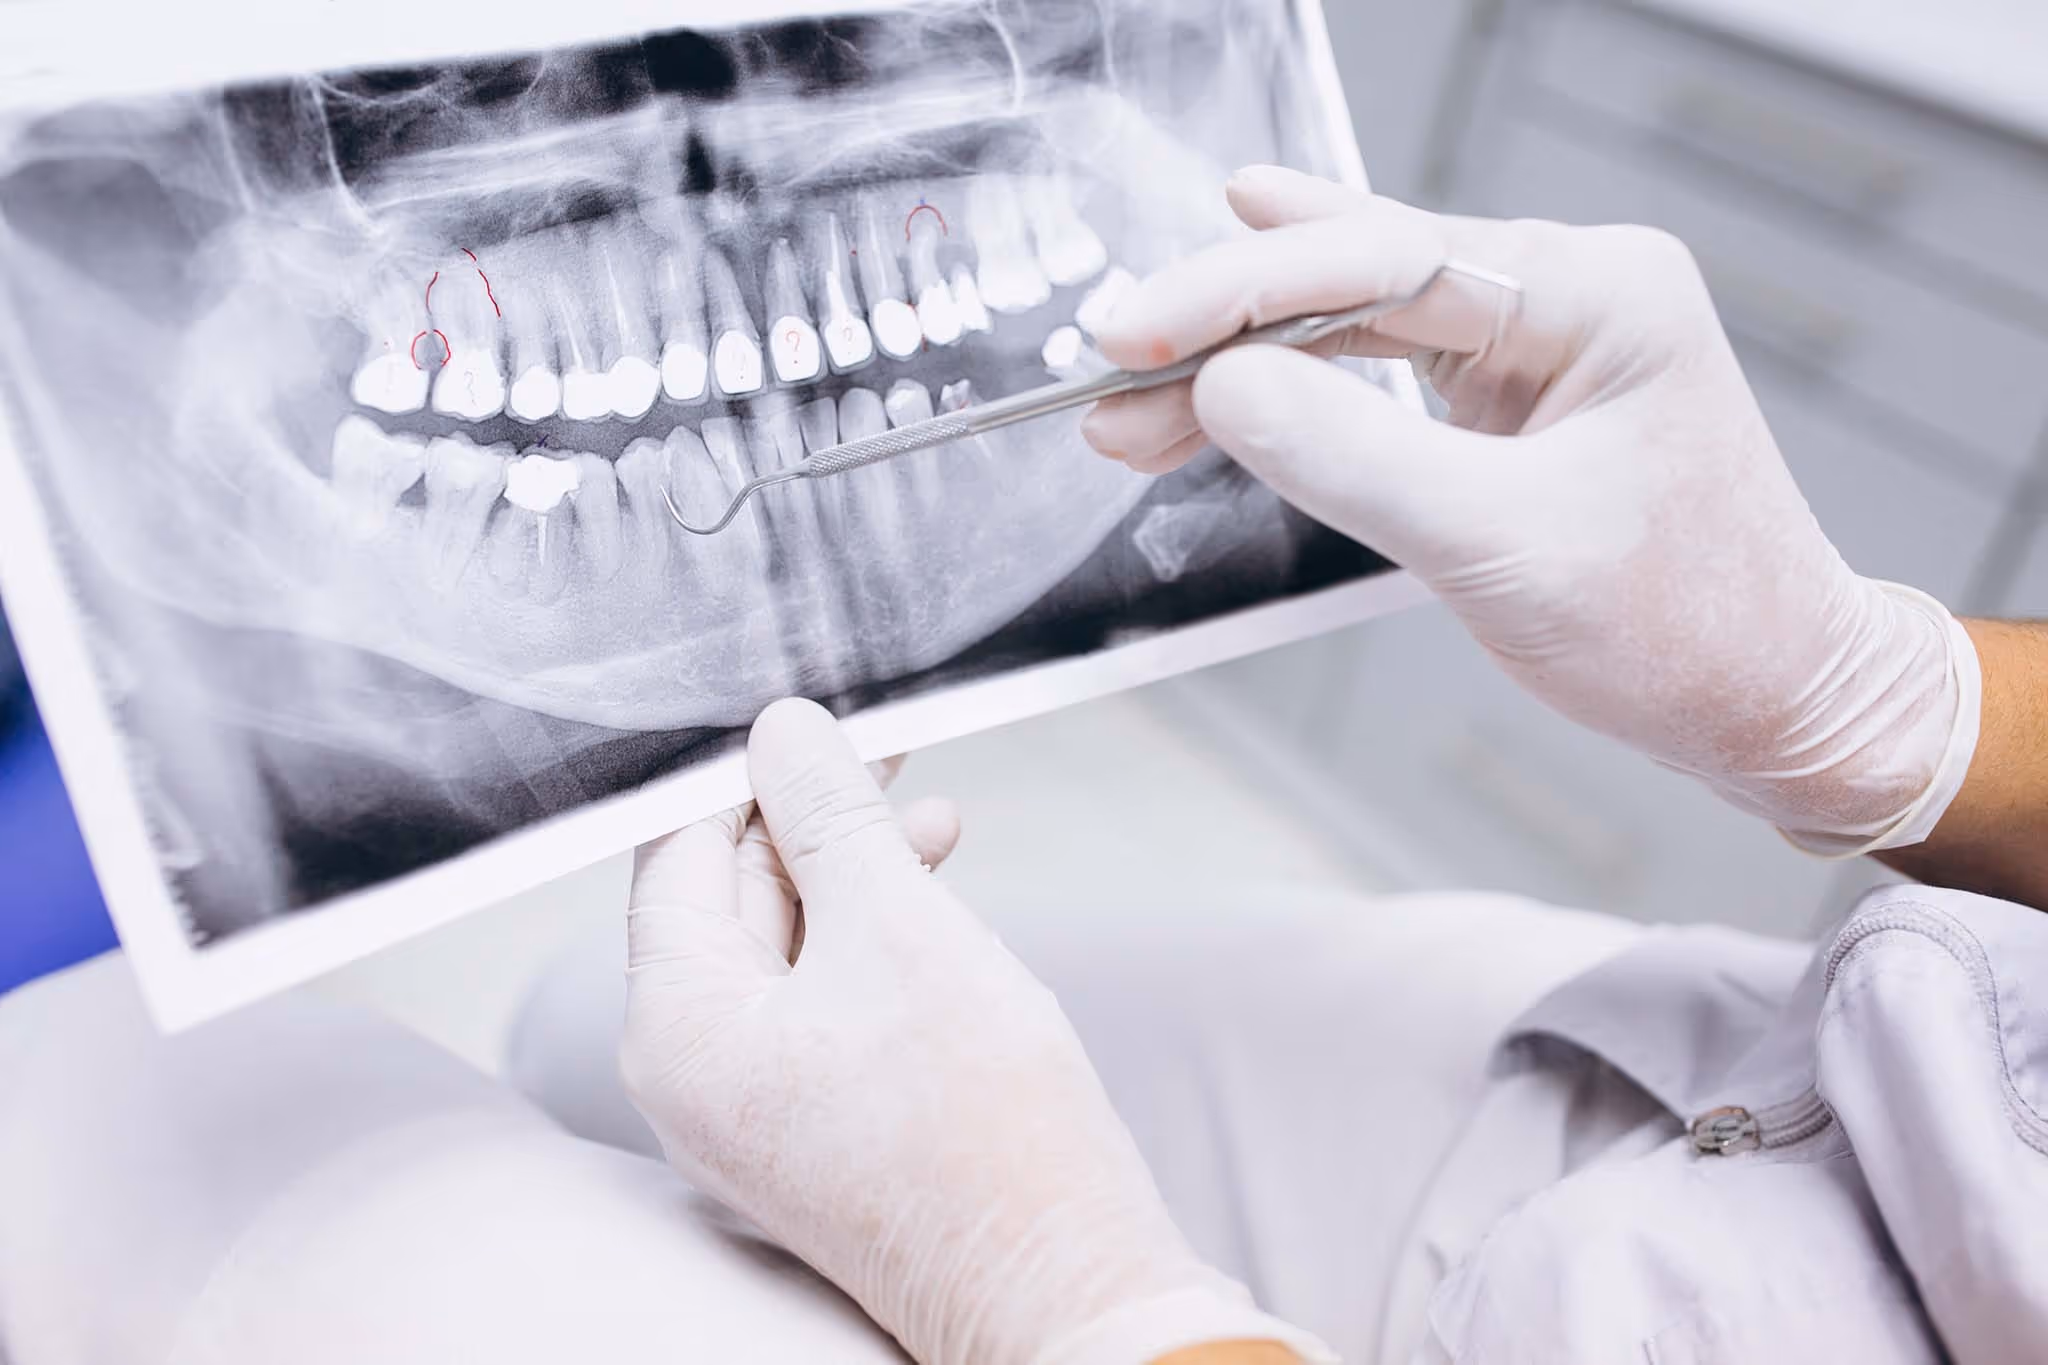

Dental x-rays